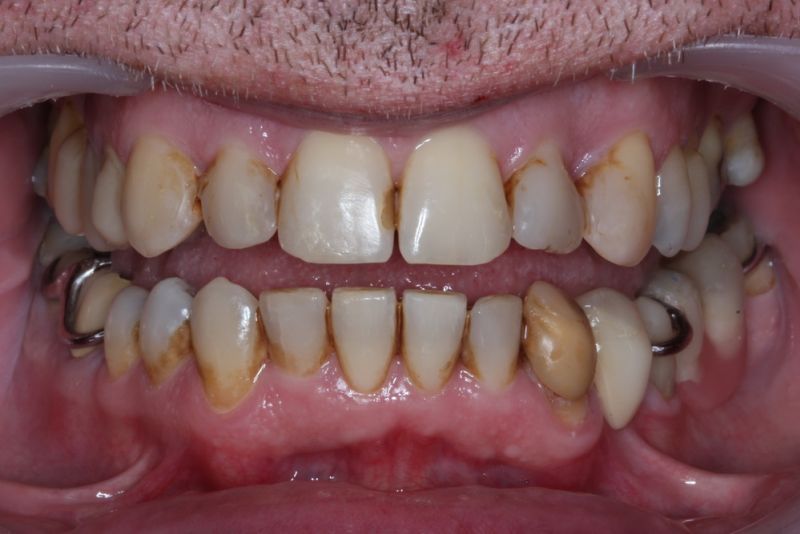

Der Patient hat von einem CMD Spezialisten in Bielefeld einen Aufbissbehelf erhalten. Den hat der Patient mit Zellstoff unterfüttert, weil der Aufbissbehelf so unterschiedlich hoch war, dass der Patient es vor Schmerzen mit dem Aufbissbehelf nicht ausgehalten hat.

Der Patient hat in den Jahren 2012-2014 eine kieferorthopädische Erwachsenenbehandlung durchführen lassen.

Erkennbar ist die massive Abweichung der habituellen Bisslage von der neuromuskulär zentrierten Bisslage.